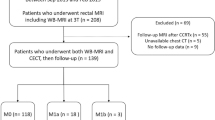

This prospective study was conducted from November 2016 to April 2018 and recruited 203 consecutive patients with biopsy-proven rectal adenocarcinomas (assessed by rigid proctoscopy to be up to 15 cm from the anal verge) to undergo [18F]fluorodeoxyglucose (FDG)-PET/MRI. The inclusion criteria were as follows: (1) age more than 18 years, (2) ready to sign the informed consent form, and (3) able to undergo the staging examinations (PET/MRI and ceCT) at a maximum interval of 2 weeks. The exclusion criteria were as follows: (1) previous treatment for rectal cancer, including endoscopic resection, and diagnosed synchronous non-colorectal neoplasia and (2) PET/MRI contraindications. The patients’ selection flowchart is presented in Fig. 1. The institutional review board approval was obtained, and this study was registered at clinicaltrial.gov under the identification number NCT02537340.